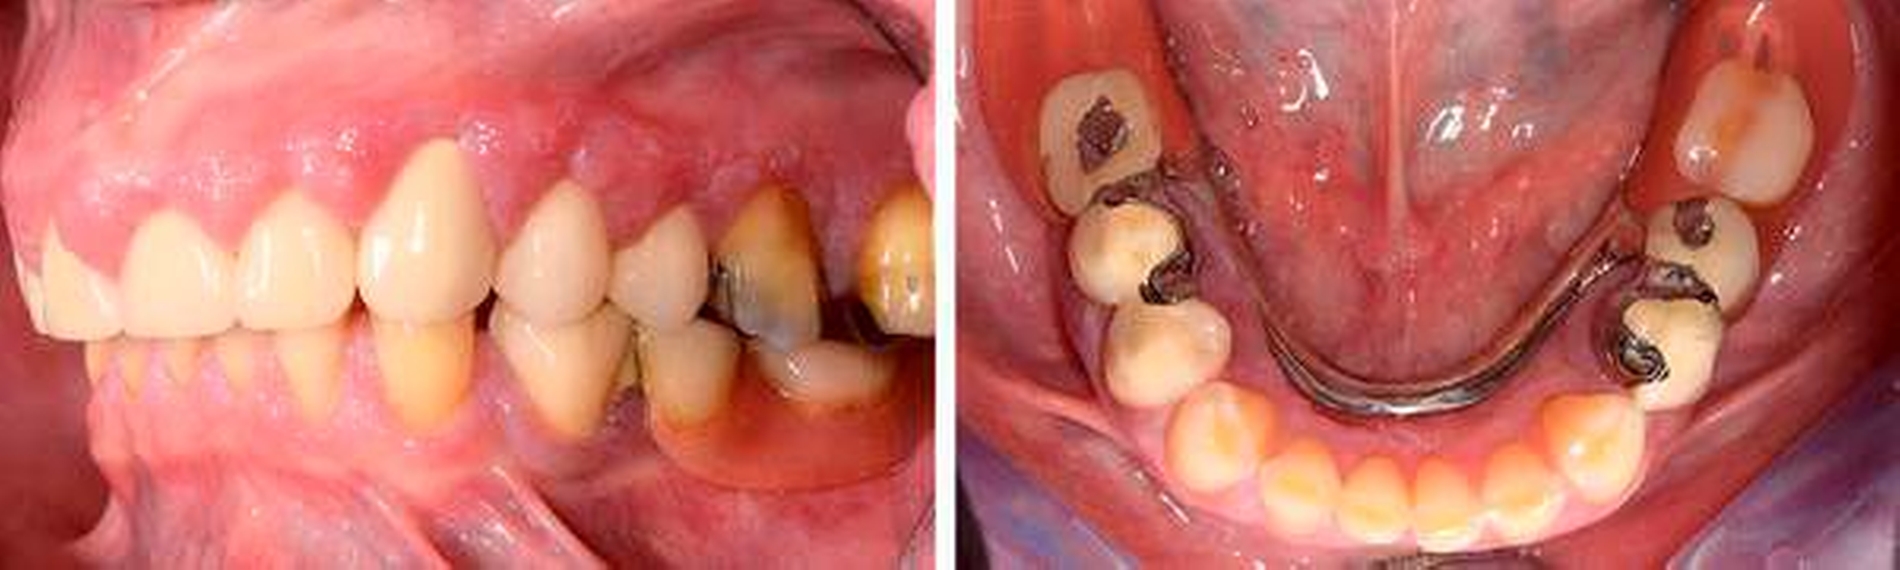

Befund: Bei der klinischen Untersuchung zeigten sich vestibulär und oral im Bereich der Papillen und der befestigten Gingiva generalisierte Gingivawucherungen im Oberkiefer (OK) und im Unterkiefer (UK). Die Interdentalräume waren aufgrund der Gingivawucherungen nicht für Hygienehilfsmittel durchgängig. Der Parodontale Screeningindex (PSI) wies im OK die Codes 3/3/4, im UK die Codes 3/1/3 auf. Der daraufhin erhobene Parodontalstatus (Abbildung 2) zeigte im OK Sondierungstiefen bis 7 mm mit Furkationsbeteiligungen Grad I (Zähne 16, 26, 27). Im UK betrugen die Sondierungstiefen bis zu 4 mm. Die Zahnbeweglichkeit an den Zähnen 16, 26 (Grad I) und 27 (Grad II) war erhöht.

Der Plaqueindex PCR betrug 72 Prozent [O`Leary TJ et al., 1972] und der gingivale Blutungsindex GBI 75 Prozent [Ainamo J et al., 1975]. Das alio loco angefertigte Orthopantomogramm (Abbildung 3) zeigte horizontalen Knochenabbau bis zu einem Drittel der Wurzellänge in beiden Kiefern. Die Zähne 16 und 26 wiesen einen Knochenabbau > 2/3 der Wurzellänge auf. Am Zahn 27 mesial erreichte der Knochenabbau die Wurzelspitze; zudem war der Zahn elongiert und wies eine Kippung nach distal auf. In einer ersten Einzelzahnprognose wurden alle Zähne mit Ausnahme von Zahn 27 als sicher eingestuft. Prothetisch war die Patientin im OK mit einer Brücke (13 bis 15), Kronenblöcken (21/11, 21/22, 24/25) und Amalgamfüllungen an den Zähnen 16 und 26 sowie im UK mit einer geschiebeverankerten Modellgussprothese versorgt.

Sechs Wochen nach Deep Scaling und Root Planing erfolgte eine zweite Reevaluation mit Befunderhebung [MacNeil RL et al., 1999]. Erhöhte Sondierungstiefen lagen nur noch an den Zähnen 27 (5 mm) und 34 (4 mm) vor (Abbildung 4). Die Gingivawucherungen hatten sich vollständig zurückgebildet (Abbildungen 5a bis 5e). Die Plaque- und Blutungsindizes waren niedrig und stabil (20 Prozent). Abschließend wurde eine PZR zusammen mit einer subgingivalen Reinigung an den Zähnen 27 und 34 durchgeführt. Die Prognose der Zähne mit Ausnahme des Zahns 27 ist weiter als sicher einzustufen. Zahn 27 bleibt kritisch. Dies ist durch den Attachmentverlust von 10 mm mesial und den Lockerungsgrad II begründet. Aufgrund der kompromittierenden parodontalen Situation und der eingeschränkten prothetischen Wertigkeit könnte bei Beschwerden an Zahn 27 neben einer chirurgischen Taschenelimination auch eine Extraktion erwogen werden. Die bisherige prothetische Versorgung könnte dann im Konzept einer verkürzten Zahnreihe belassen werden [Fueki K et al., 2015; Levey C et al. 2015]. Da die Patientin vorerst keine weitere Therapie an Zahn 27 wünschte, musste an dieser Stelle von einer chirurgischen Taschenelimination abgesehen und der Zahn belassen werden.